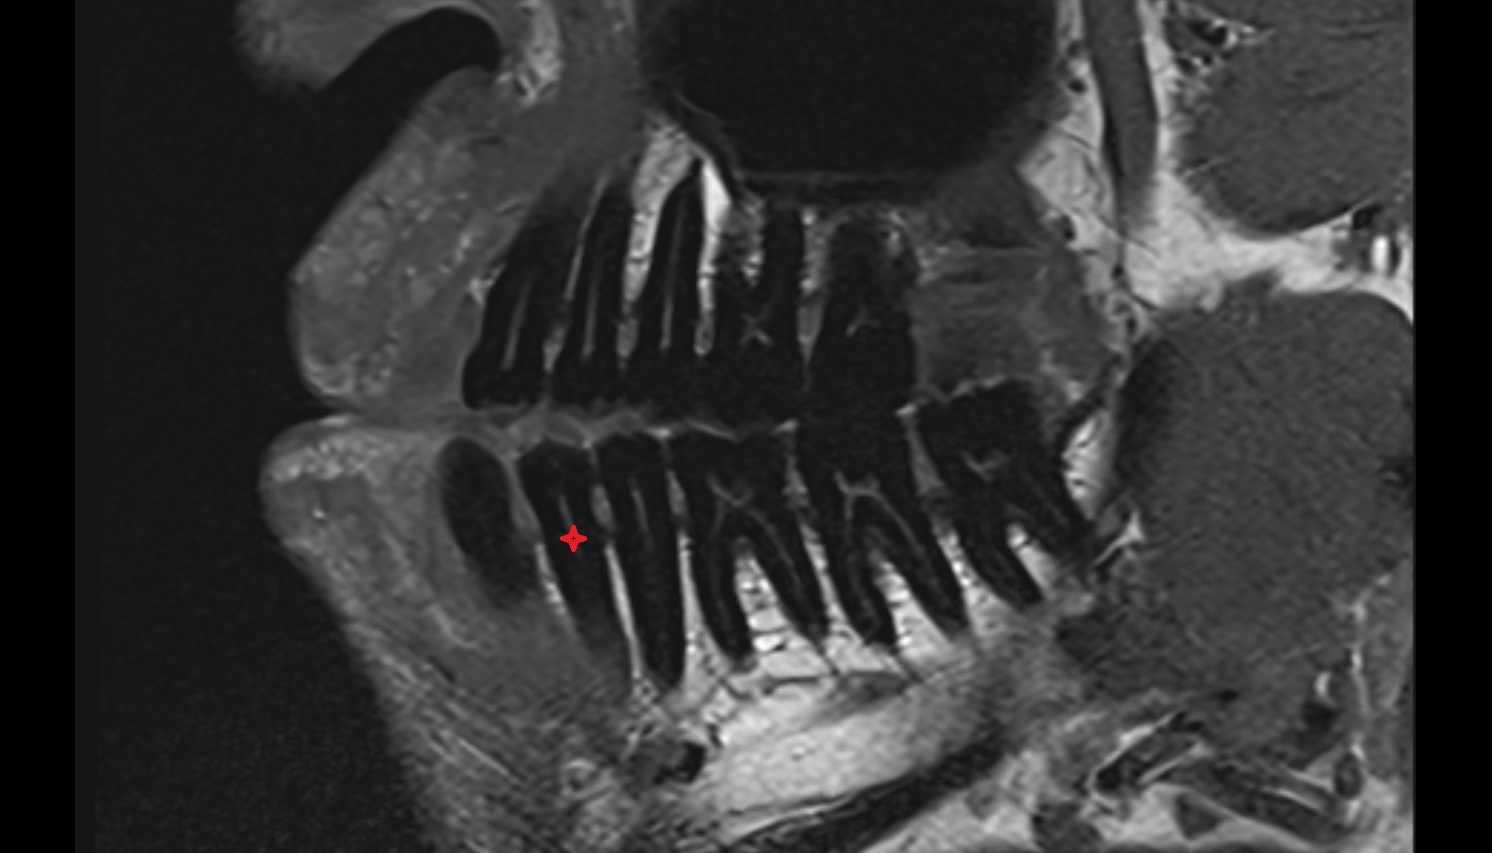

- Central inferior incisor tooth

- Central superior incisor tooth

- Inferior canine tooth

- Inferior cornu of thyroid cartilage

- Inferior first premolar tooth

- Inferior second molar tooth

- Inferior second premolar tooth

- Inferior third molar tooth

- Lateral inferior incisor tooth

- Lateral superior incisor tooth

- superior canine tooth

- Superior first molar tooth

- Superior first premolar tooth

- Superior second molar tooth

- Superior second premolar tooth

- Superior third molar tooth

- Root of lower molar tooth

- Lower molar apical foramen

- Upper premolar apical foramen

- Root of upper molar tooth

- Root canal of upper molar tooth

- Dental pulp of upper molar tooth

- Dental pulp of upper premolar tooth

- Enamel of canines tooth

- Enamel of lower molar tooth

- Enamel of upper molar tooth

- Enamel of upper incisor tooth

- Enamel of lower canines tooth

- Enamel of lower incisor tooth

- Enamel of lower premolar tooth

- Dental pulp of lower molar tooth